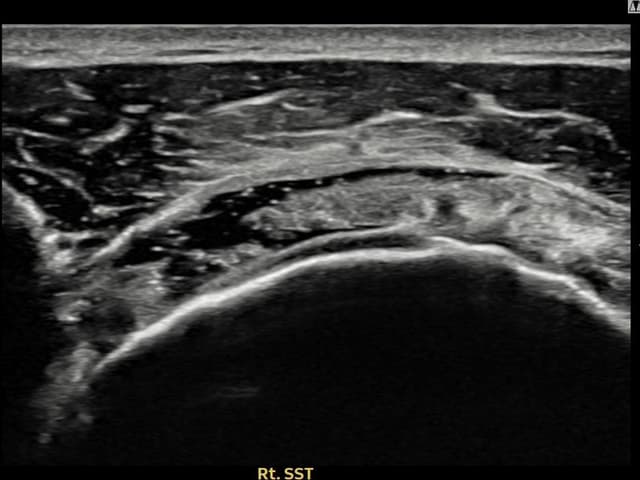

[経過期間: 24.04.26~24.07.05]

[縫縮術] 超音波検査にて右 棘上筋腱 관절면측 광범위 部分断裂(16mm × 5mm (腱厚の約75%欠損))を確認。縫縮術施行後、腱の連続性が回復し、日常生活に復帰されました。